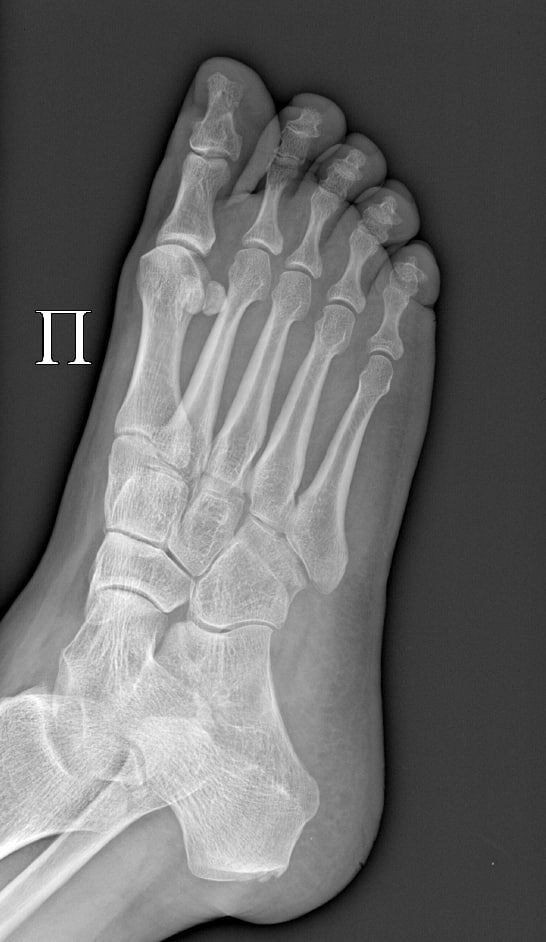

А в субботу поехала кататься на велосипеде в парке, неудачно свернула и грохнулась на бок. Плечи и ребра спас руль, а вот нога сильно болела. Я сначала думала отлежаться, но мама посоветовала все же сходить в травм.пункт. Сходила, сделали рентген, диагноз - закрытый перелом основания 5 плюсневой кости правой стопы без смещения. Такой перелом еще называется "перелом Джонса". Тут же наложили гипс и сказали не наступать на ногу. О своем опыте посещения травм.пункта расскажу в следующий раз. Там есть свою нюансы.